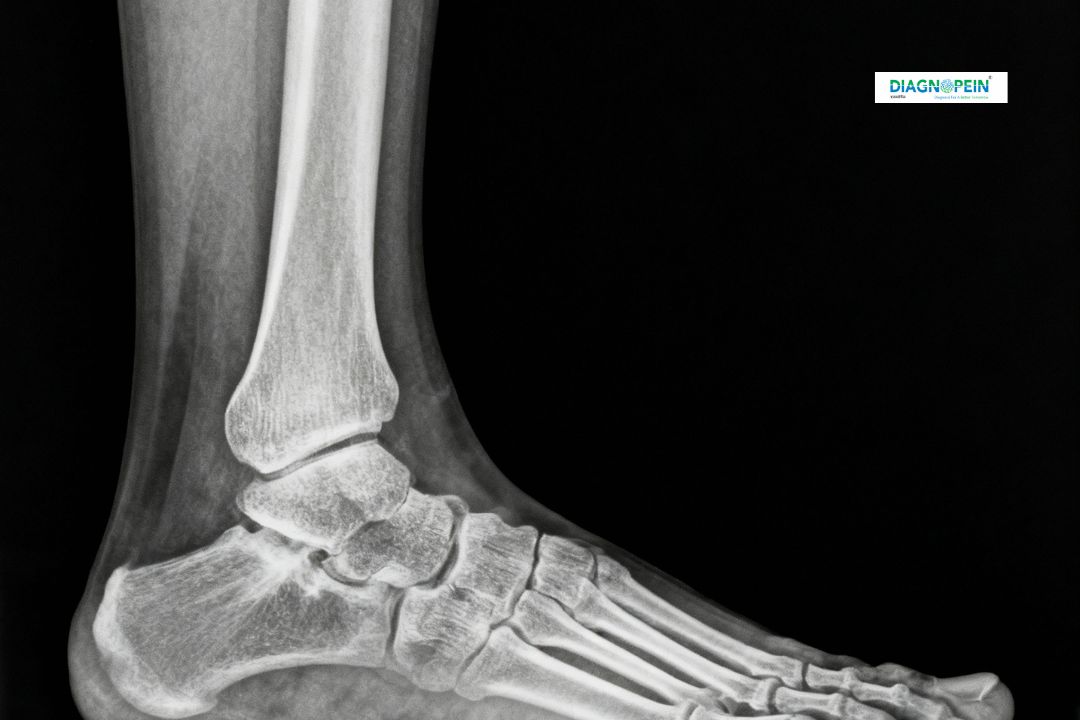

The X-Ray Right Foot Lateral View (LAT) is a specialized radiographic examination designed to capture a side-view image of your right foot. This view allows doctors to analyze the bones, joints, and soft structures in accurate alignment. At Diagnopein Karad, we use high-resolution digital equipment for low radiation exposure and clear imaging results.

This test is commonly recommended if you experience persistent pain, swelling, injury, or deformity in your right foot. The lateral view provides a detailed visualization of the heel, toes, and arch, helping identify fractures, dislocations, and signs of arthritis or bone infections.